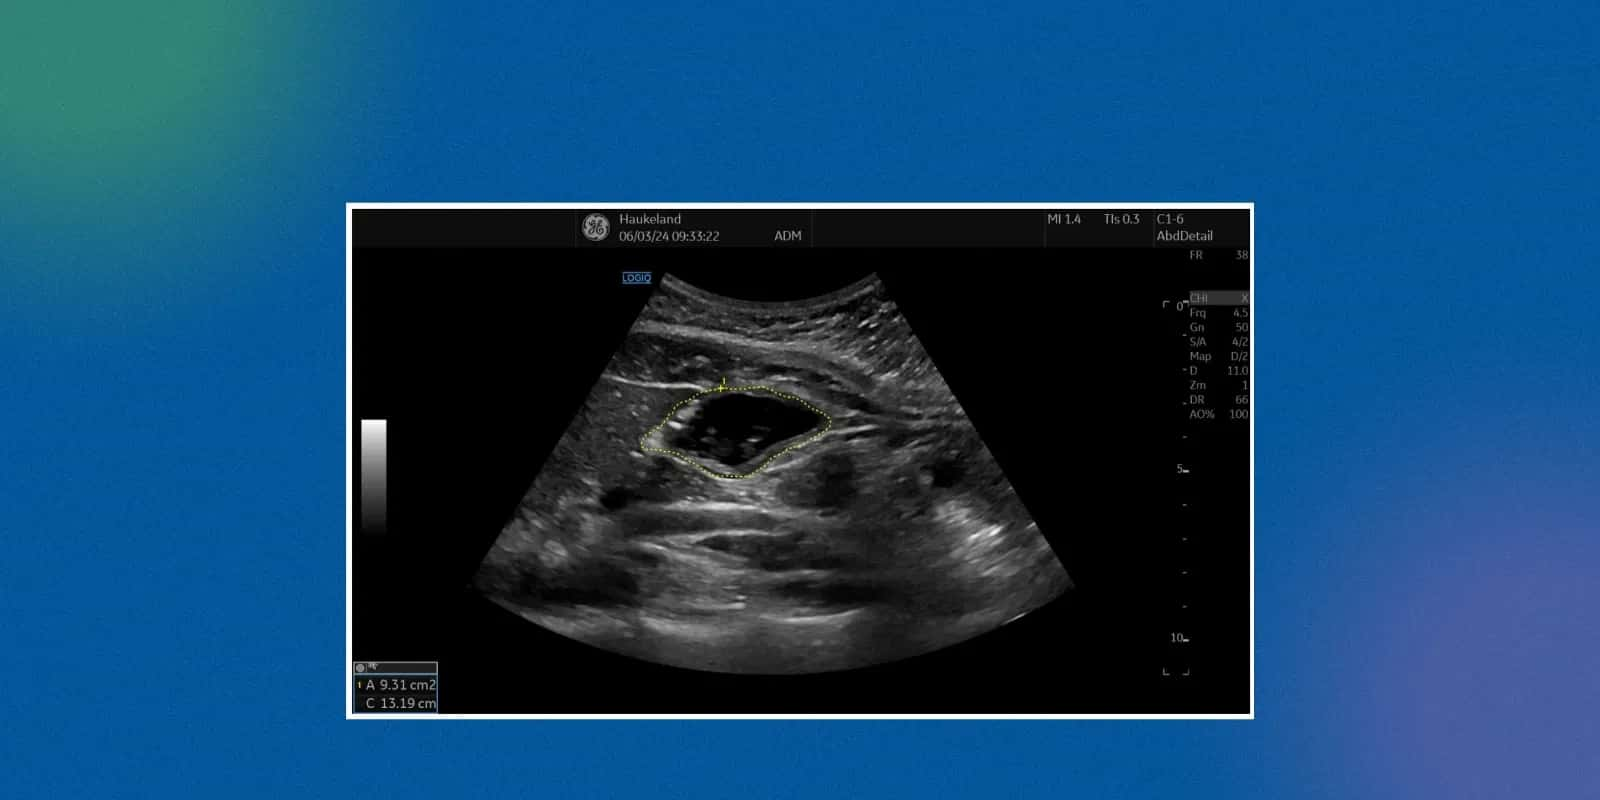

A non-invasive imaging test, such as an ultrasound of the whole abdomen, or whole abdomen USG, uses sound waves to form pictures of the organs of the abdomen. The technique does not use radiation, as in the case of X-rays, and is therefore safe for both adults and children.

The process is easy and generally takes 15-30 minutes. A trained technician or radiologist applies a gel to the abdomen to enhance the transmission of sound waves. A transducer, a handheld device, is then placed and moved on the surface of the abdomen.

The reflected lines of sound create real-time images on a monitor, which are then recorded as the ultrasound report of the whole abdomen. The procedure is painless, but patients may experience mild pressure with the movement of the probe on tender regions.

Interpretation of an ultrasound report of the whole abdomen requires medical knowledge; however, patients can identify key terms. Reports tend to describe organ size, the structure of the organs, the existence of cysts, stones, or abnormal growths.

If the report mentions terms like “hyperechoic” or “hypoechoic,” these describe how tissues reflect sound waves. Doctors interpret these findings to confirm or rule out disease.